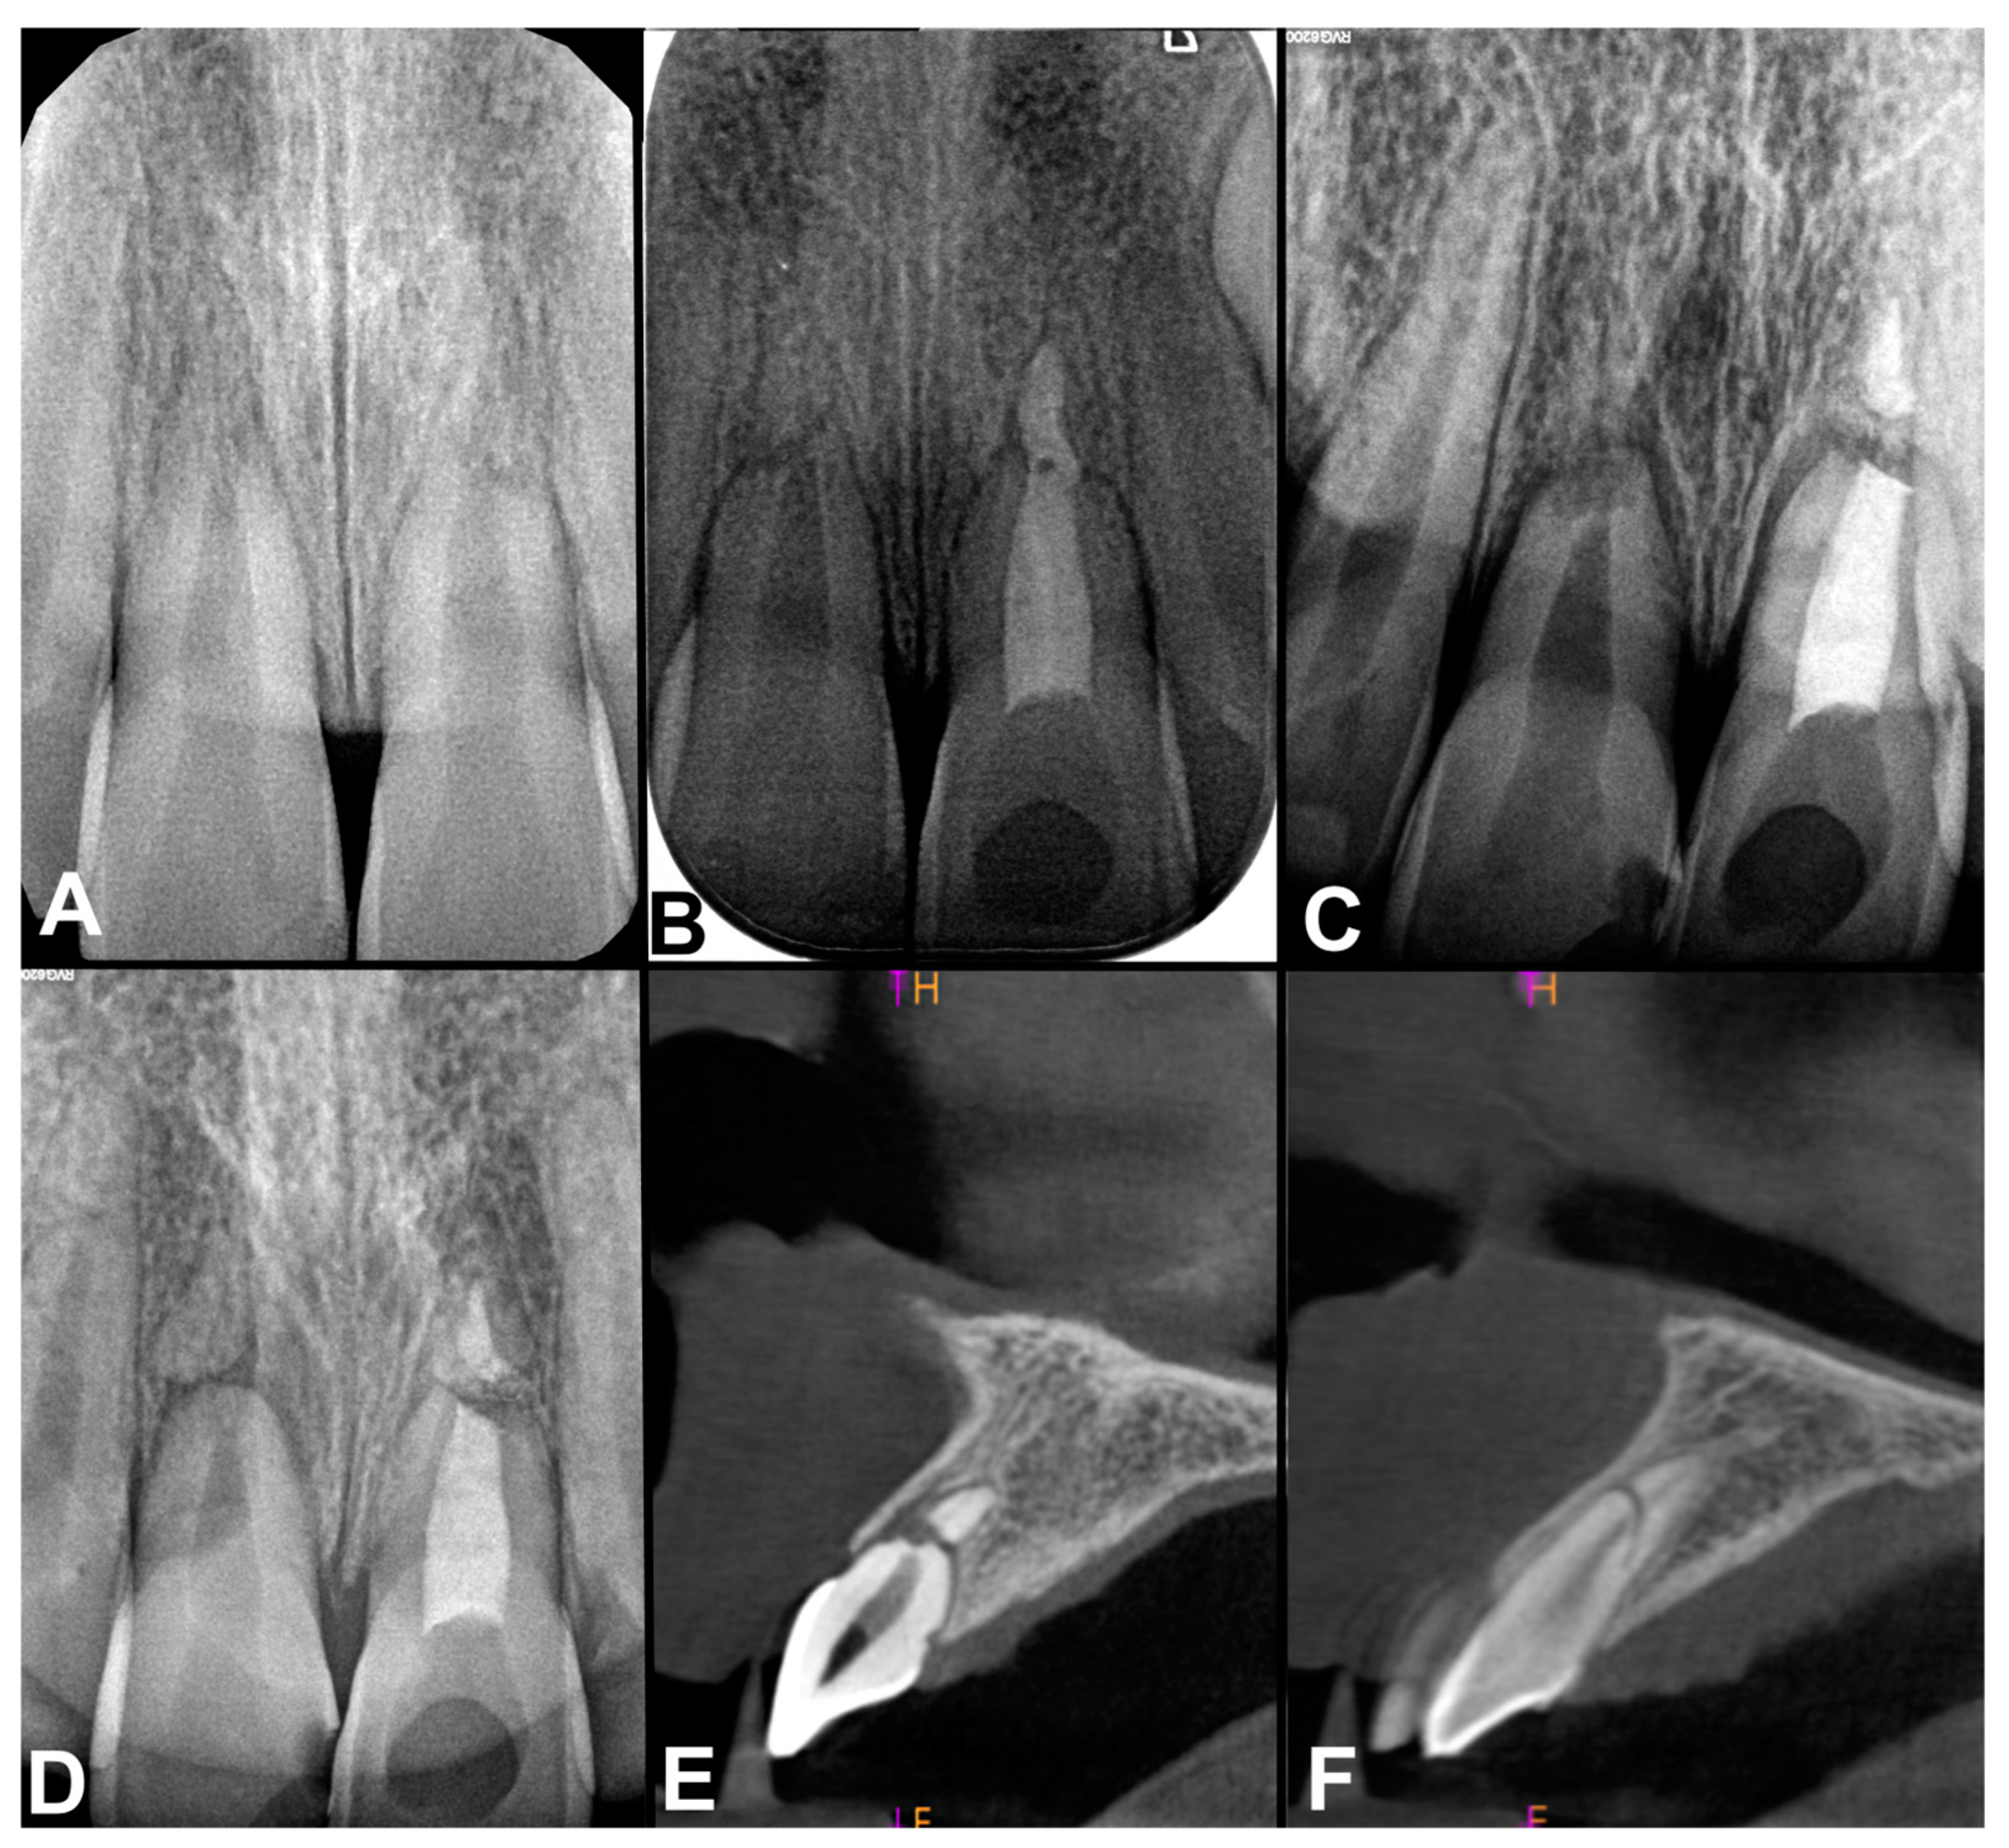

2.2. Case Report 2